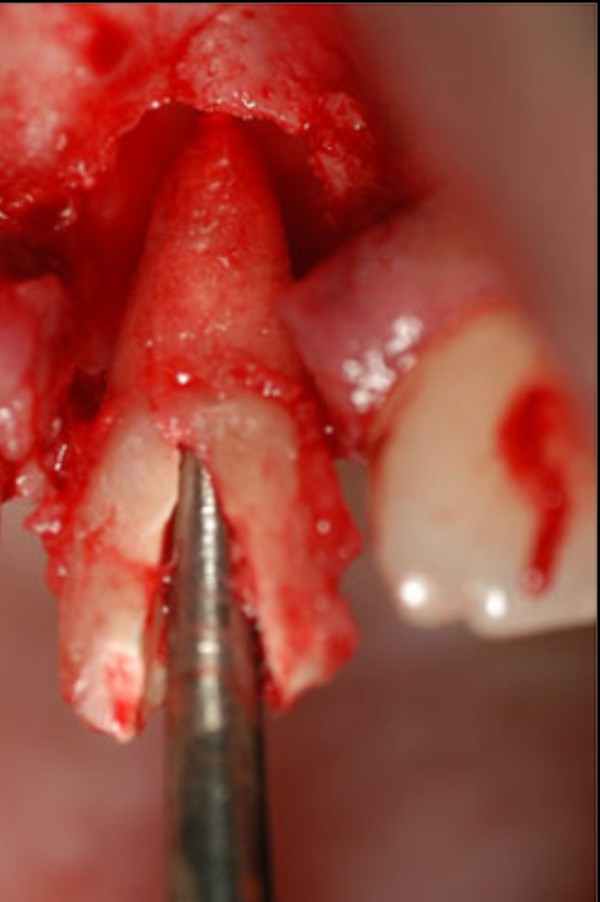

Las extracciones dentarias o EXODONCIAS, son habitualmente realizadas mediante la utilización de instrumentos denominados FÓRCEPS, los que instalados en el cuello de la pieza dentaria a extraer, son movidos de manera oscilante en el eje del diente, lográndose después de un corto período de tiempo, quitar al mismo de la cavidad ósea que lo aloja, en una operación que se denomina LUXACIÓN o AVULSIÓN. FÓRCEPS EN BOCA Esta AVULSIÓN, se produce debido a que el hueso es elástico. Sin embargo , gran parte de las veces esa elasticidad no es suficiente y se parte o rompe la «corteza ósea» que rodea al diente, en su región más cercana a la «zona cortante» del mismo.Esa ruptura o fractura, es favorecida por el uso de los Fórceps, dado que sus «mordientes» se sitúan muy cerca de del hueso. .FÓRCEPS ROMPIENDO LA TABLA TABLA ROTA La idea de crear un instrumento que impida dicha fractura, se basa en la certeza de que cuanto más adentro del diente, y cuanto más cerca de la punta del diente, se efectúe la fuerza de AVULSIÓN, menos posibilidades de fractura existirán por una simple cuestión de física básica: CUANTO MÁS LARGO SEA EL BRAZO DE POTENCIA DE UNA PALANCA, MENOS ACCIÓN TENDRA EL BRAZO DE RESISTENCIA….POR LO TANTO SERÁ NECESARIA MENOS POTENCIA PARA VENCER LA RESISTENCIA… O SEA, CON MOVIMIENTOS MAS DELICADOS , LOGRAREMOS EL MISMO EFECTO. ESQUEMA DE DIENTE MOSTRANDO LA ACCIÓN DE LAS FUERZAS DE UN FÓRCEPS. ESQUEMA DE DIENTE MOSTRANDO LA ACCIÓN DE FUERZAS DE UN AIDA Cuando la especialidad IMPLANTOLOGÍA, no se había desarrollado tal como ahora la conocemos, la fractura de esa «corteza ósea» denominada TABLA EXTERNA O INTERNA del PROCESO ALVEOLAR, carecía de importancia ya que la cicatrización se produce irremediablemente en ausencia de infecciones Sin embargo, a la luz de los conocimientos actuales, la preservación de dichas TABLAS, son de capital importancia para la realización de un IMPLANTE INMEDIATO(Implante colocado en el mismo acto quirúrgico que la extracción), y para el logro de su INTEGRACIÓN Y ESTÉTICA futura. Es por eso que exponemos ante las autoridades competentes, la idea de patentar un instrumento como el que denomino: AVULSIONADOR INTRADENTARIO ATRAUMÁTICO …cuyas características principales son: MATERIAL: ACERO QUIRÚRGICO 316 LONGITUD TOTAL:13 mm PUNTA ACTIVA: 6 mm FORMA DE PUNTA ACTIVA: HELICOIDAL DECRECIENTE DOS GROSORES DE PUNTA. INSTRUMENTO AD HOC Por acción de las espiras , el instrumento se fija en las paredes del canal dentario, produciendo un anclaje que permite la AVULSIÓN. CRESTA ÓSEA COMPLETAMENTE CONSERVADA